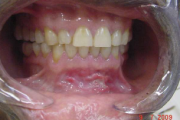

Crohni tõbi